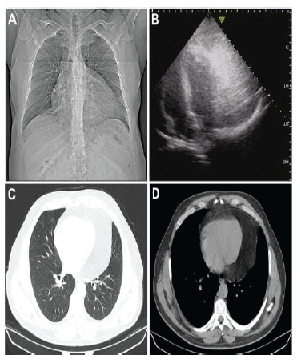

| Figure 1: Preoperative imaging studies: (A) Chest X-ray showing enlargement of the cardiac silhouette; (B) Echocardiography examination showing a echogenic large intrapericardic mass; (C, D) CT-scan showing intrapericardic mass mimicking pericardial effusion. |